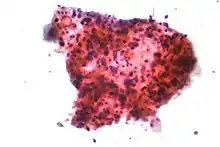

سرطانهای ریه بر اساس نوع وابسته به بافتشناسی ردهبندی میشوند.[8] این ردهبندی برای تعیین نوع مدیریت بیماری و پیشبینی نتایج بیماری حائز اهمیت است. اکثریت قریب به اتفاق سرطانهای ریه کارسینوماها هستند —بدخیمیهایی که در نتیجه بافت پوششی پدید میآیند. — کارسینومهای ریه بر اساس اندازه و شکل سلولهای بدخیم دیده شده توسط یک متخصص هیستوپاتولوژی در زیر یک میکروسکوپ ردهبندی میشوند. دو رده گسترده آنها کارسینوم ریه سلول-غیرکوچک و کارسینوم ریه سلول-کوچک میباشد.[45]

_by_core_needle_biopsy.jpg.webp)

در کارسینوم ریه سلول-کوچک (SCLC)، سلولها در بر گیرنده دانههای ترشح عصبی (کیسههای کوچک در بر گیرنده هورمونهای درونتراو عصبی) میباشند که این تومور را با سندروم درونتراو/پارانئوپلاستیک مرتبط ساختهاست.[48] اغلب موارد در مجاری هوای بزرگتر (نایژههای اولیه و ثانویه) پدید میآیند.[10] این سرطانها خیلی سریع رشد پیدا میکنند و خیلی زود در همان مراحل اولیه بیماری گسترش مییابند. شصت تا هفتاد درصد مبتلایان دچار بیماری دگردیس هستند. این نوع سرطان ریه بشدت با سیگار کشیدن در ارتباط است.[1]